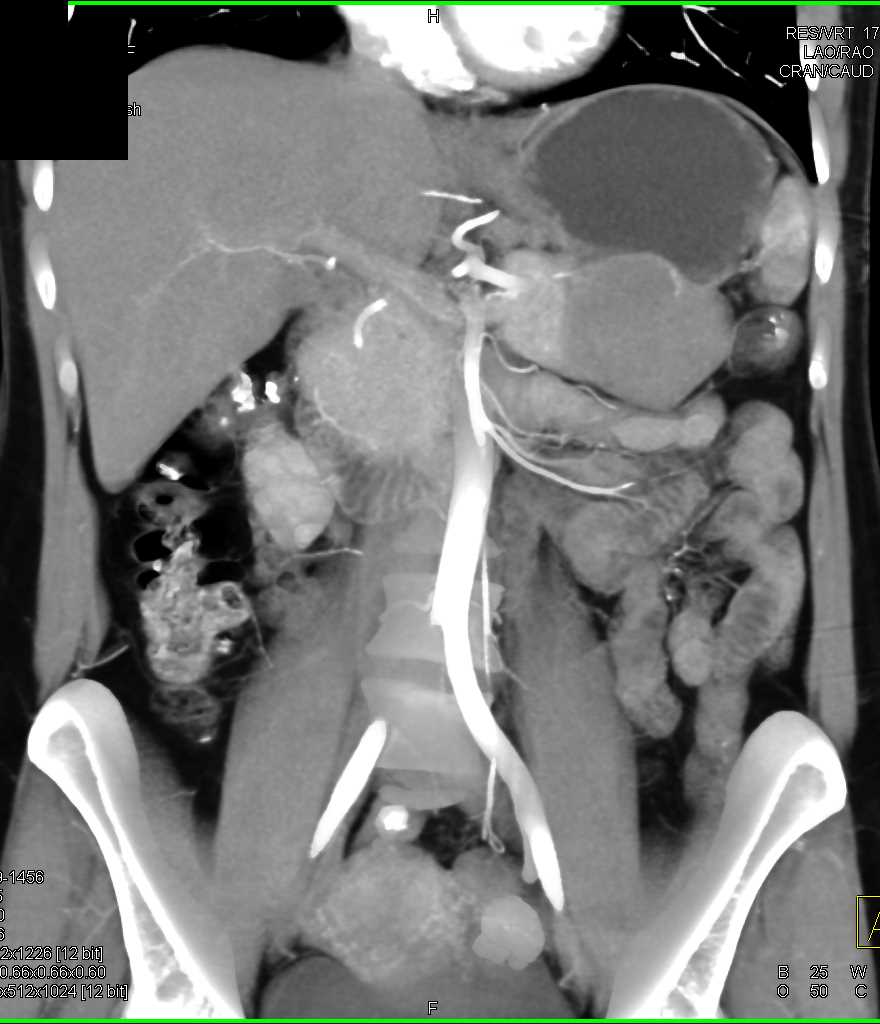

Mass Pushes on Tail of Pancreas was Ganglioneuroma